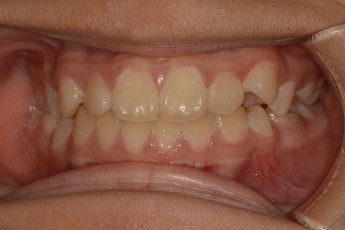

Before

After